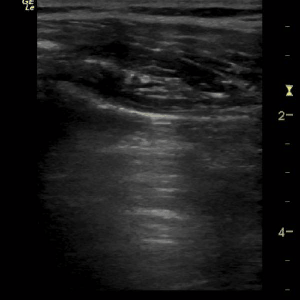

Barcode or stratosphere sign

Typically found in patients with pneumothorax. The lung sliding is absent and the sand-like appearance beneath the pleural line is replaced by parallel lines.